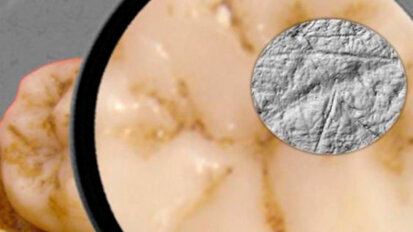

L’analisi dei denti mostra i vantaggi dell’uomo moderno su quello di Neanderthal

TÜBINGEN, Germania: esaminando i fossili di molari attraverso un’analisi della loro micro usura, un team internazionale di ricercatori ha tratto ...